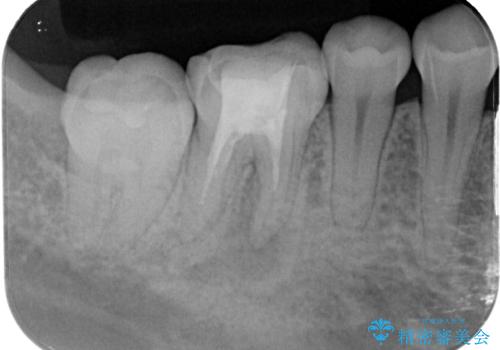

レントゲン検査では、根の先端に透過像(根尖病変の可能性)が見られ、過去の治療ではラバーダム防湿が使用されていなかったそうです。

当院ではラバーダム防湿をし、根管内の感染源をしっかりと除去するために再根管治療を行いました。